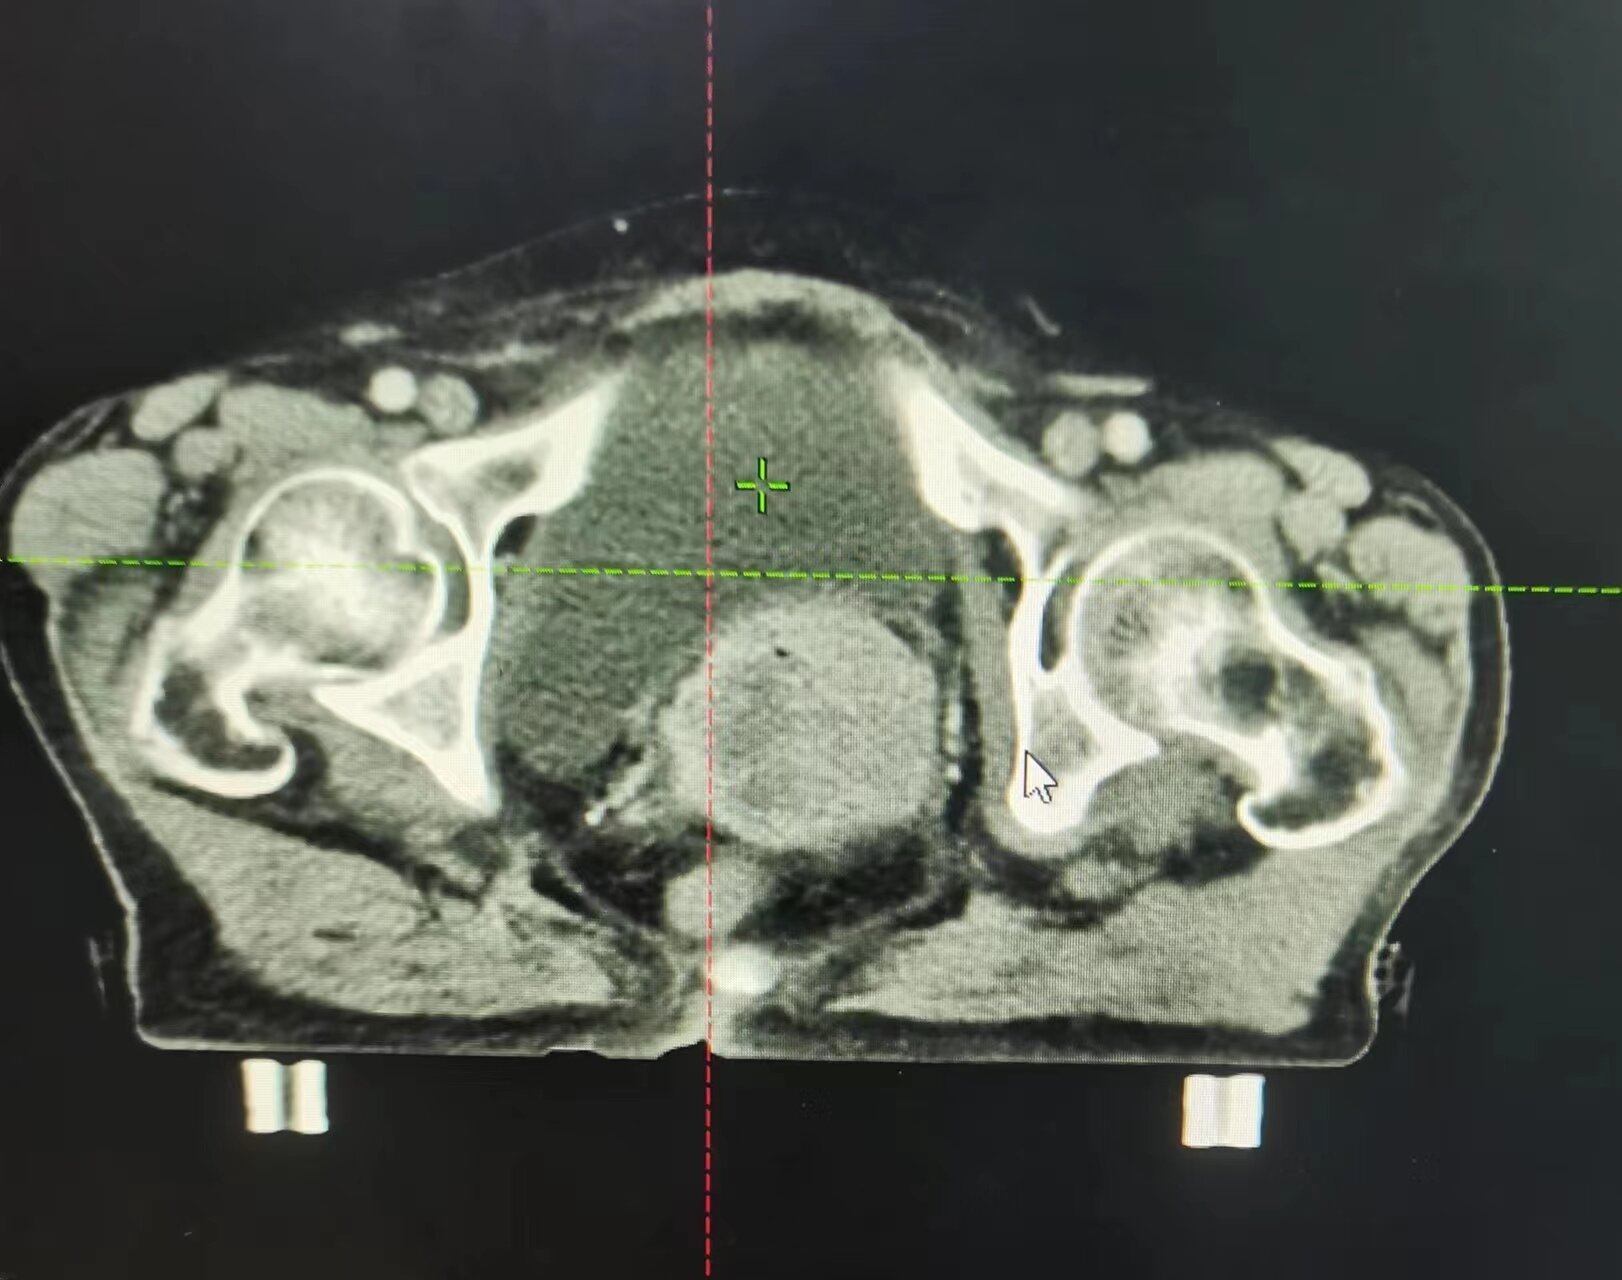

近日,75歲的宮頸癌晚期患者朱阿姨,接受市二院放療科的16次精準(zhǔn)放療后,復(fù)查CT顯示:腹膜后及盆腔轉(zhuǎn)移淋巴結(jié)消失,宮頸腫瘤較前明顯縮小。

朱阿姨被確診宮頸癌后,每天嚴(yán)重的陰道出血及腹部疼痛,使她受盡癌痛的折磨并且心情極度抑郁。3月中旬老人突然腹痛伴陰道大出血,家屬急忙帶朱阿姨來到市二放療科找到趙亮主任,入院后明確診斷為宮頸癌腹膜后及盆腔部位淋巴結(jié)轉(zhuǎn)移。

因老人出血量較大,趙亮接診后立即給予止血治療,出血暫時控制住了,但是腫瘤消不掉,出血現(xiàn)象還是會反復(fù),甚至可能出現(xiàn)危及生命的大出血。考慮到患者病期晚、年齡大、合并基礎(chǔ)疾病多,趙亮帶領(lǐng)科室團(tuán)隊經(jīng)過仔細(xì)討論及評估病情后,決定盡快進(jìn)行三維精準(zhǔn)放射治療及同步化療,同時給予止血及對癥支持治療。

開始朱阿姨非常沮喪,一度想放棄治療,趙亮耐心地跟她溝通,用科室治療成功的案例來鼓勵她。經(jīng)過5天的治療,患者局部出血大大改善,治療過程中也沒有感到不適,放療11次后患者陰道出血狀況完全緩解,腹部疼痛較前明顯改善。朱阿姨非常高興,逢人便說,放射治療解決了她的問題。家屬看到朱阿姨的變化,連連驚嘆:“真是沒有想到有這么好的治療效果,開始我們還擔(dān)心放療的副作用,沒想到現(xiàn)在技術(shù)這么好,副作用這么小,現(xiàn)在什么不舒服都沒了。”目前,患者正在非常積極的繼續(xù)配合后續(xù)相關(guān)治療。